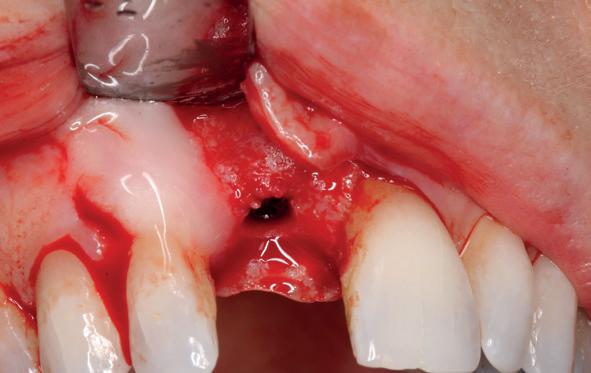

2. Beoordeling van zacht weefsel en botcontour.

Na het klinische onderzoek volgde het röntgenologisch traject. De CBCT liet precies zien wat we al vreesden: een front waarin het bot onregelmatig was, duidelijke radiolucenties rond de pijlers en een infectiegebied dat zich onder vrijwel de gehele brug had verspreid. Tegelijkertijd was er ook potentie. Net voldoende botstructuur om immediate implantaatplaatsing te overwegen, mits alles perfect gepland zou worden.